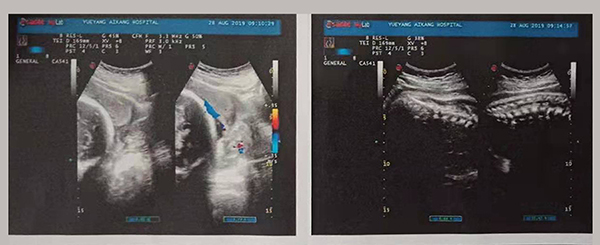

近日,岳陽愛康醫(yī)院產科團隊成功搶救了一名完全性前置胎盤的產婦。完全性前置胎盤是妊娠期的嚴重并發(fā)癥,是分娩期子宮切除的一個重大高危因素之一,是引起孕產婦死亡和圍生兒死亡的重要原因之一。

2019年8月24日,易女士出現陰道流血,在岳陽縣人民醫(yī)院住院,住院期間予以安治、止血,于26日出院。28日早晨6點再次出現陰道流血,量多、顏色鮮紅、三片衛(wèi)生巾均浸透,遂來岳陽愛康醫(yī)院產科。

易女士一進入病房就引起了岳陽愛康醫(yī)院產科主任高君萍的高度重視,考慮到手術的風險大,手術過程復雜,有可能出現新生兒窒息、產婦大出血等危及母嬰生命的并發(fā)癥,甚至切除子宮可能。在檢驗科充分術前配血、血漿的準備及全院MDT(多學科聯合會診),立即進行手術。

術中,擺在產科團隊面前的第一個嚴峻考驗出現了,整個子宮下段前壁膨隆血管怒張!迅速設計子宮切口,取出胎兒,面臨又一嚴峻的考驗,胎盤大面積植入整個子宮下段前后壁,迅速行雙側子宮動脈下行支結扎,迅速人工剝離胎盤以及卵圓鉗鉗夾剩余胎盤組織,植入的胎盤處理干凈后子宮下段前后壁多處肌層缺損伴有大量活動性出血,迅速行子宮下段整形修復縫合止血……不得不說產婦是幸運的,婦產科、手術麻醉科等多科通力合作,經過約2小時的手術及搶救止血,術中共計出血1500ml,輸懸浮紅細胞4個單位,終于保得母女平安,并完美的保留了子宮。易女士術后恢復良好,對婦產科的精湛技術贊不絕口!